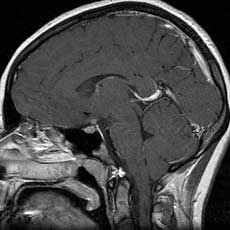

T1 sagittals post gad

Findings:

Enhancement and thickening of the inferior hypothalamus and pituitary infundibulum (arrow).